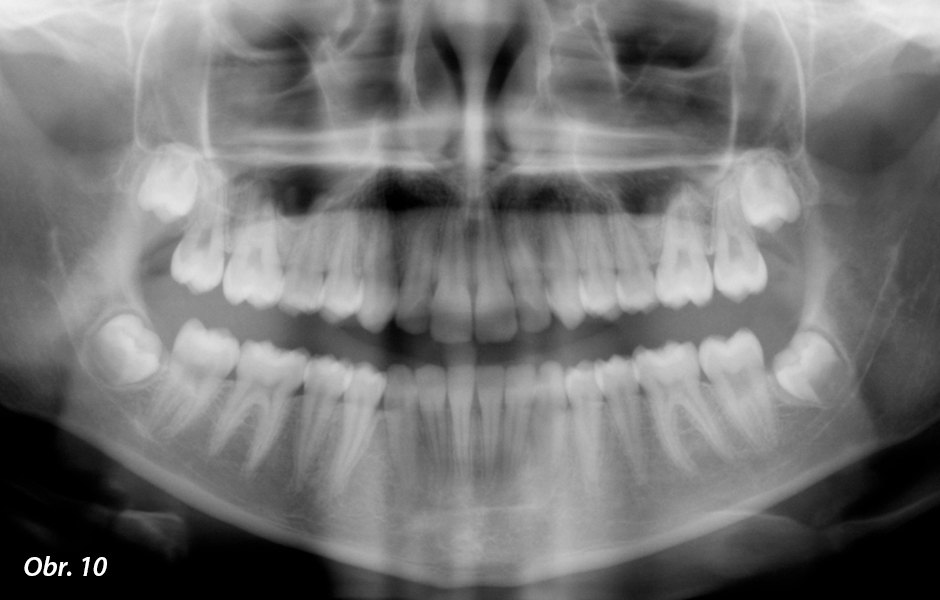

Panoramatický rentgenový snímek před léčbou

Klinické vyšetření odhalilo zubní malokluzi třídy I se zvýšeným předkusem v důsledku náklonu horních řezáků. Hluboký skus souvisí se zvýšenou Speeovou křivkou s extruzí spodních řezáků. Dále docházelo k extruzi pravých horních premolárů. Oba oblouky byly na frontální rovině zúženy a horní stoličky byly mediálně otočeny. Byl zjištěn také dento-dentální nesoulad s mandibulárním přesahem asi 1 mm. Radiografické vyšetření ukázalo skeletální malokluzi třídy I u normodivergentní pacientky a kruhovou, dobře definovanou ohraničenou nekontrastní oblast (folikulární cysta) obklopující korunku mandibulárního pravého prvního premoláru bez vytlačení zubů (obr. 5–7).